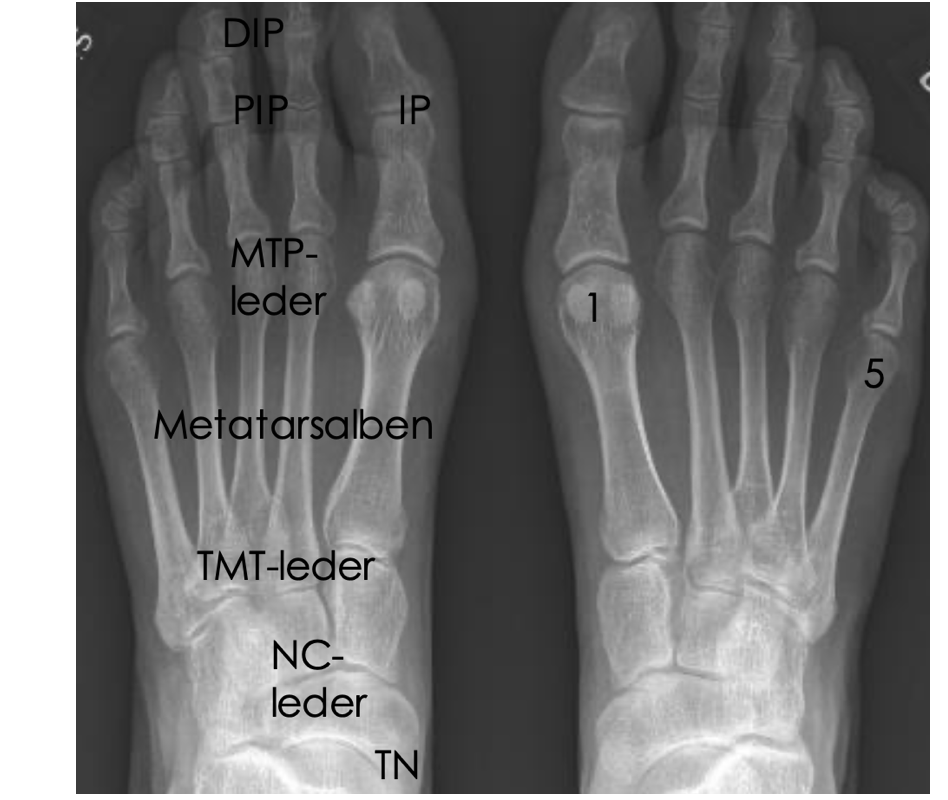

vad heter alla leder i benet?

Subtalarleder

NC-leder = naviculare-cuneiforme-led

TMT-leder = tarsometatarsallederna

Stortåns grundled: MTP1 = metatarsofalangealled 1

MTP 2-5 = metatarsofalangeallederna

Tåleder = PIP (proximal interfalangealled) och DIP (distal interfalangealled)